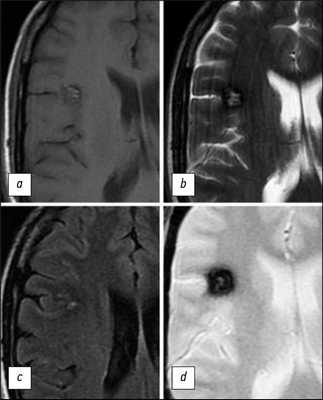

ПРИМЕНЕНИЕ МАГНИТНО-РЕЗОНАНСНОЙ ТОМОГРАФИИ ДЛЯ ВИЗУАЛИЗАЦИИ КАВЕРНОЗНОЙ МАЛЬФОРМАЦИИ

В 1987 г. D. Rigamonti и соавт. [16] продемонстрировали, что МРТ при уровне магнитного поля 1,5 Тл является наиболее чувствительным и специфичным методом в отношении выявления КМ. Эти исследования положили начало использованию данного метода для диагностики КМ. Было установлено, что визуализация с использованием T2-взвешенных изображений (T2-ВИ) чувствительна на 100% в отношении КМ, тогда как чувствительность T1-взвешенных изображений (T1-ВИ) значительно ниже.

Отложения гемосидерина внутри и вокруг КМ, которые считаются типичным признаком повторных субклинических кровоизлияний или лизиса эритроцитов, обеспечивают магнитную восприимчивость этого патологического образования, особенно при высокой напряжённости магнитного поля. Неоднородность магнитного поля в присутствии гемосидерина также способствует дифференциации кровотока и эффектов гемосидерина в КМ (рис. 2) [16, 17].

![]()

Рис. 2. МР-томограммы головного мозга в аксиальной плоскости, выполненные в режимах Т1-ВИ (a,c), Т2-ВИ (b), T2*GRE (d), демонстрируют более детальную визуализацию структуры КМ (тот же случай, что и на рис. 1). На изображениях визуализируется очаговое образование характерной ячеистой структуры с гипоинтенсивным периферическим сигналом на Т2-ВИ. Последовательность T2*GRE подчеркивает «цветущий» эффект гемосидерина.

Было выдвинуто предположение, что данные МРТ соответствуют гистологически подтверждённым результатам изучения КМ с приемлемой достоверностью. Со временем МРТ стала рассматриваться в качестве метода выбора диагностики в плане идентификации и характеристики КМ.

В целом комбинация ободка пониженного сигнала с сетчатым ядром смешанной гипер- и гипоинтенсивности на T2-ВИ с высокой вероятностью является диагностическим признаком наличия КМ. Для очагов КМ меньших размеров вместо этого оценивается точечная область гипоинтенсивности на Т2-ВИ. Сопровождающий образование вазогенный отёк в перифокальных отделах, который проявляется повышенной интенсивностью сигнала на T2-ВИ, а также эффект массы обычно не проявляются даже при достаточно больших размерах очага, если не было относительно недавних кровоизлияний (рис. 3) [17, 22].